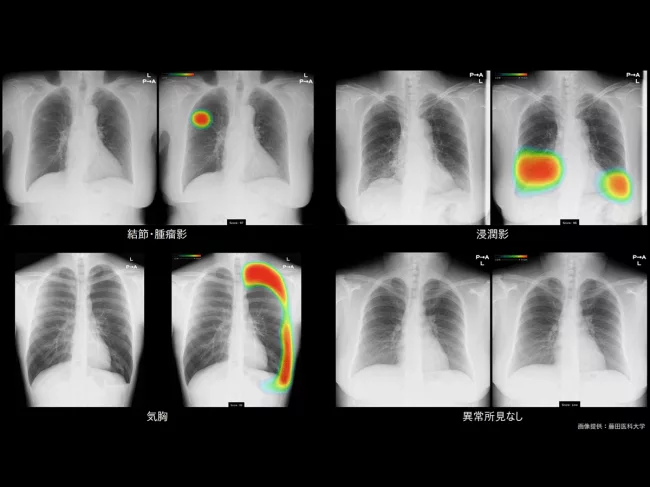

Chest X-ray analyzed using CXR-AID

Fujifilm, Lunit get nod for collaborative AI-powered chest X-ray analysis system in Japan

Fujifilm Holdings Corp. has bagged the Japanese Pharmaceuticals and Medical Devices Agency (PMDA)’s approval for CXR-AID, its artificial intelligence (AI) powered chest X-ray analysis system developed in collaboration with Lunit Inc. Read More